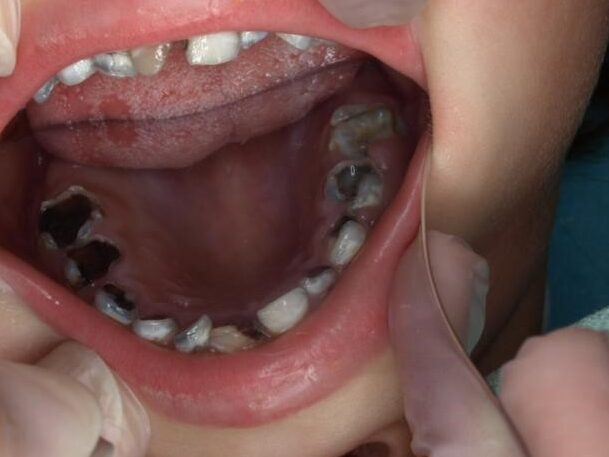

Cambios de color en los dientes

Uno de los primeros signos de caries en niños es un cambio de color en los dientes. Los dientes pueden volverse amarillos, marrones o incluso negros. Estos cambios de color son causados por la desmineralización del esmalte dental debido a la acción de los ácidos producidos por las bacterias.

Pérdida de sustancia y rotura del esmalte dental

A medida que la caries avanza, puede causar la pérdida de sustancia y la rotura del esmalte dental. Los dientes pueden volverse frágiles y quebradizos, lo que puede llevar a la formación de cavidades y a la necesidad de tratamientos dentales más invasivos, como empastes o extracciones.

Borde amarillo, marrón o negro en los dientes

Otro signo de caries en niños es la aparición de un borde amarillo, marrón o negro en los dientes. Este borde es causado por la acumulación de placa dental y la desmineralización del esmalte dental. Si se deja sin tratar, esta área puede convertirse en una cavidad dental.